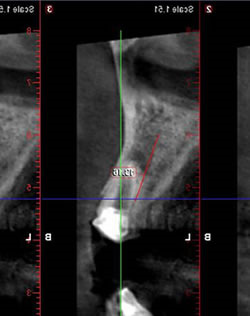

CT像です。歯根の周りには骨がありますので、抜歯即時インプラント埋入の適応です。

術後のCT像です。いいポジションにはいりました。(インンプラントを専門に行っている先生はわかるのですが一般の人には専門的でわかりませんね)。抜歯即時インプラントは難度の高いオペですが、患者さんにとって、切開しないため痛みもなく、当日仮歯も入り、オペの回数を減らせるのでとても有効な治療方法です。